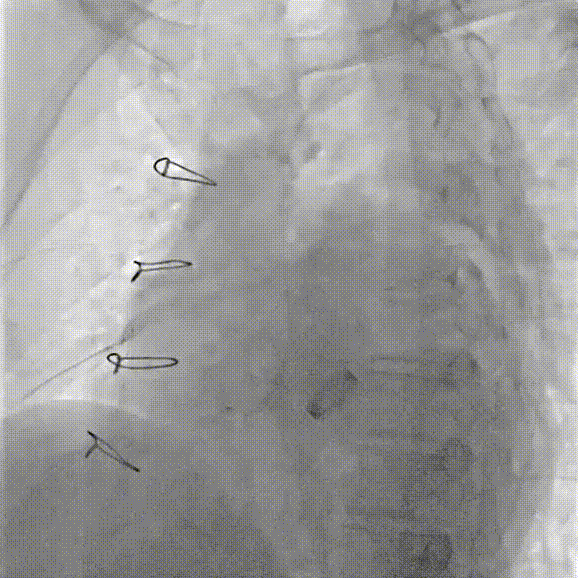

术中操作